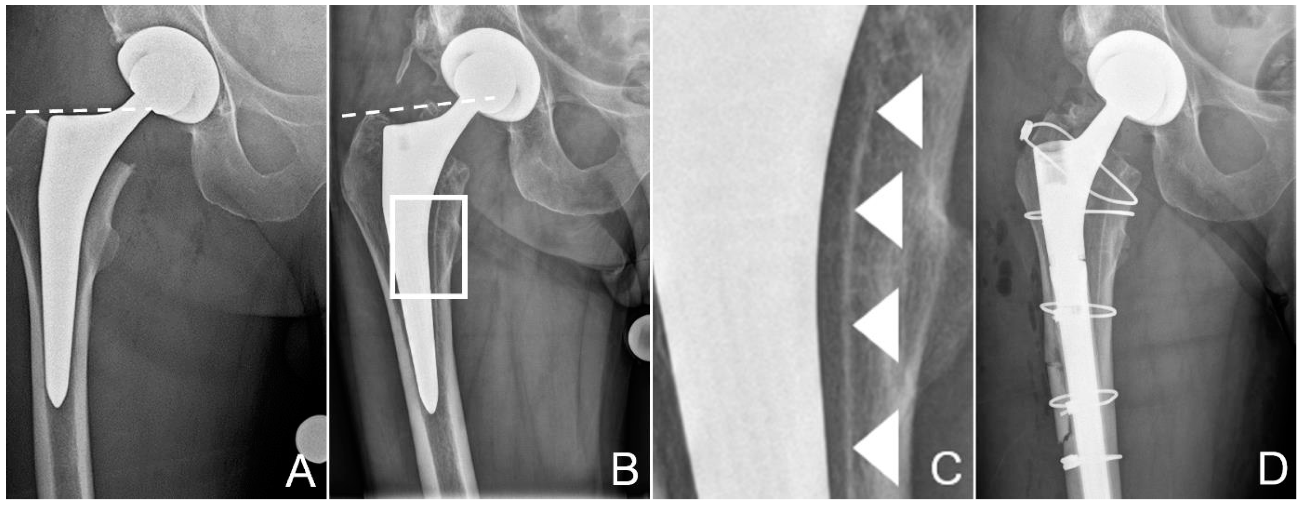

2.1. Case Description